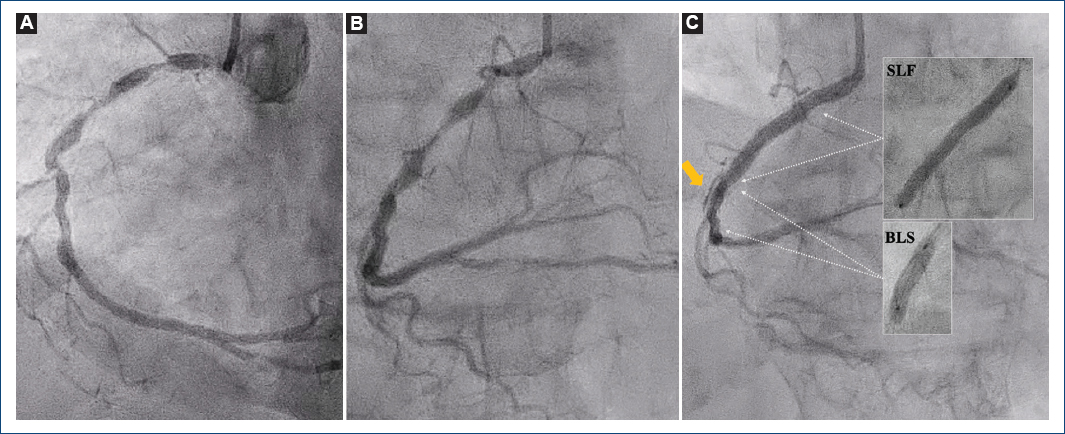

Mujer de 83 años que ingresó por un infarto de miocardio sin elevación del segmento ST. La angiografía coronaria reveló lesiones severas, anguladas y calcificadas en la arteria coronaria derecha (Fig. 1A y B). Se realizaron predilataciones con balones no distensibles y de corte mediante un extensor de catéter guía, seguido del implante de un stent liberador de sirolimus, lo que ocasionó una disección coronaria distal (Fig. 1C). Durante su tratamiento, la guía de angioplastia y el nuevo stent fueron retirados accidentalmente. Tras recolocar el material y aparentemente implantar el stent, la disección persistió y el dispositivo no pudo ser localizado mediante angiografía coronaria (Fig. 1C).

Figura 1 A y B: imágenes de la angiografía coronaria inicial que muestran lesiones calcificadas en tándem de la arteria coronaria derecha desde el ostium hasta el segmento medio, con un segmento angulado a este nivel. C: resultado angiográfico tras la implantación del primer stent liberador de fármaco (SLF) de 3.5 × 35 mm, con persistencia de la disección distal (flecha) tras la presumible implantación del segundo stent (dilatación inadvertida solo con el balón de liberación del stent [BLS]).